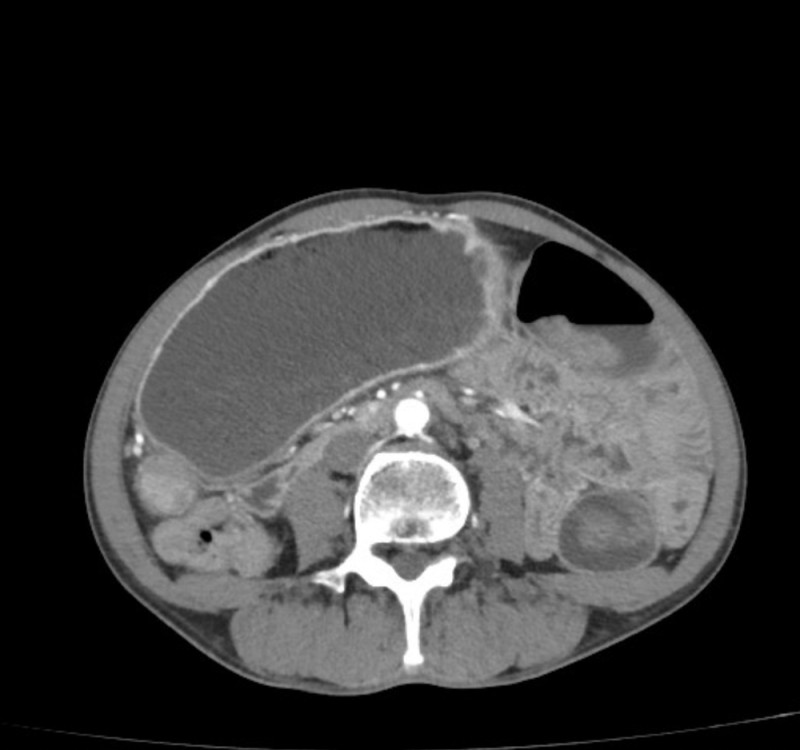

Termenul „hipodens” descrie modul în care o zonă arată pe tomografia computerizată. Acea zonă apare mai închisă la culoare decât țesutul hepatic din jur, deoarece are o densitate mai mică. Termenul nu denumește o boală, ci un aspect vizual.

Cuvântul „leziune” se referă la o modificare de structură. Poate fi un nodul mic, o formațiune bine delimitată sau o zonă mai difuză. De exemplu, un chist simplu plin cu lichid apare frecvent hipodens pe CT. Important de reținut: această descriere nu echivalează automat cu un diagnostic și nu indică neapărat o afecțiune gravă [1][2].

- CT-ul, care oferă detalii despre densitate și dimensiune;

La CT și RMN, substanța de contrast ajută la diferențiere. Unele leziuni se evidențiază clar doar într-o anumită fază de examinare. De pildă, un hemangiom poate avea un tipar diferit de alte formațiuni [1][3][4].